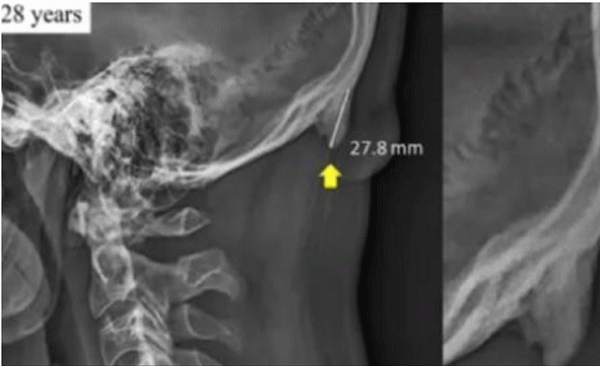

ಅಧ್ಯಯನ ಹೇಳುವ ಪ್ರಕಾರ, ಇಂದಿನ ಯುವಜನತೆ ಮೊಬೈಲ್ ಅನ್ನು ಸದಾ ಹಿಡಿದಿರುತ್ತಾರೆ. ಮೊಬೈಲ್ ನೋಡಲು ಕತ್ತನ್ನು ಕೆಳಮುಖ ಮಾಡಿಕೊಳ್ಳಬೇಕು. ಇದರಿಂದ ಬೆನ್ನು ಮೂಳೆಯ ಬದಲಾಗಿ ತಲೆ ಹಿಂಭಾಗದಲ್ಲಿರುವ ಸ್ನಾಯುವಿಗೆ ಭಾರ ವರ್ಗಾವಣೆ ಆಗುತ್ತದೆ. ನಿಧಾನವಾಗಿ ಮೂಳೆ ಆಕಾರದ ಅಂಗ ಬೆಳೆದುಕೊಳ್ಳುತ್ತದೆ ಎಂದು ಅಧ್ಯಯನ ಹೇಳಿದೆ. ಈ ಕೋಡಿನ ಉದ್ದ 3-5 ಮಿಲಿಮೀಟರ್ವರೆಗೆ ಬೆಳೆಯಲಿದೆ.

ಕಳೆದ ವರ್ಷ ಈ ಸಂಶೋಧನೆ ನಡೆಸಲಾಗಿತ್ತು. 18-86 ವರ್ಷದ 1,200 ಜನರನ್ನು ಅಧ್ಯಯನಕ್ಕೆ ಒಳಪಡಿಸಲಾಗಿತ್ತು. ಇವರಲ್ಲಿ ಶೇ. 33 ಜನರಿಗೆ ತಲೆಯ ಹಿಂಭಾಗದಲ್ಲಿ ಕೋಡು ಬೆಳೆದಿರುವ ವಿಚಾರ ತಿಳಿದುಬಂದಿದೆ.